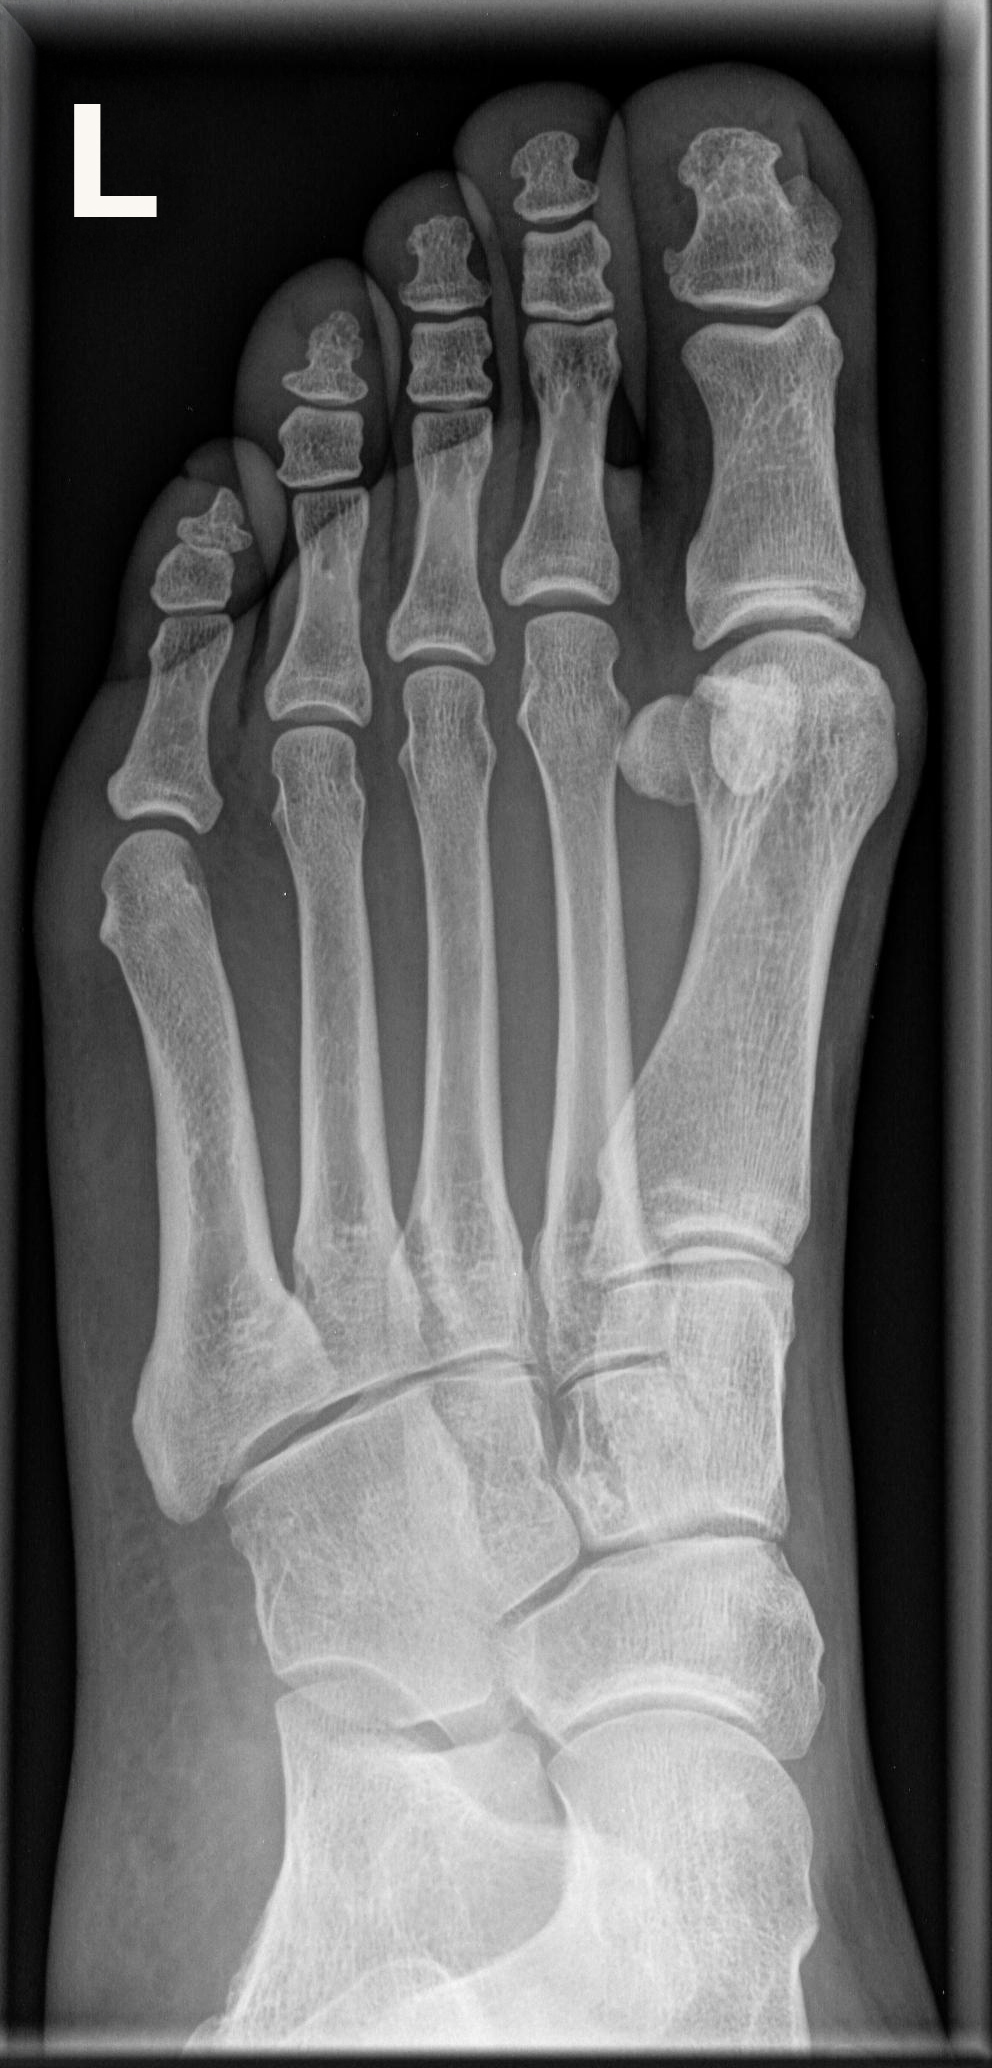

Fuß dorso-plantar (a.-p.) 1. Ebene

Fraktur, entzündliche und degenerative Veränderungen

Möglichst überlagerungsfreie Aufnahme der Mittelfußknochen, sodass die Fußwurzel-Mittelfuß- Gelenke gut beurteilbar sind.